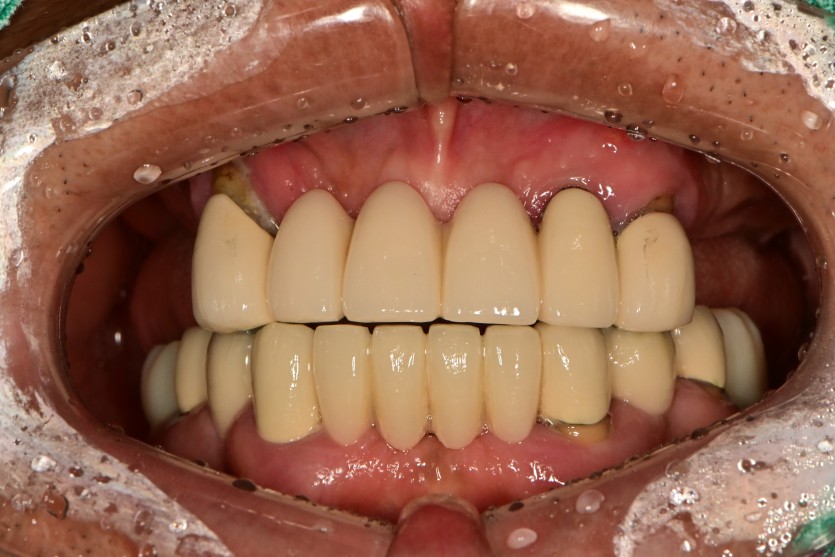

만 58세 전체 임플란트 증례

전체 임플란트 증례입니다.

16개의 임플란트로 완성하였습니다.